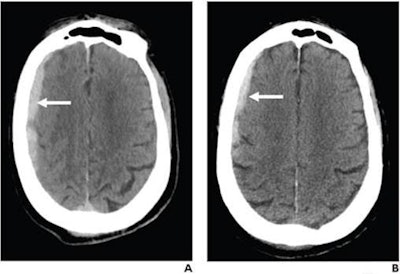

76-year-old patient, not on antithrombotic therapy, presenting to emergency department after ground-level fall (Glasgow Coma Scale of 15). Patient had no focal neurological deficit. (A) Axial slice from initial noncontrast head CT shows right frontoparietal subdural hematoma (arrow); hematoma was classified as exhibiting both regional mass effect and midline shift (not shown). (B) Axial slice from noncontrast head CT performed eight hours later shows stable size of hematoma (arrow). Patient was discharged home in stable condition two days later. Images and caption courtesy of the American Roentgen Ray Society.The group found that frequency of brain bleeds in patients who had experienced these types of falls but had good neurological status on presentation to the emergency department did not differ significantly between individuals on antithrombotic therapy and those not on it (4.4% vs. 3.1%, p = 0.24). But patients on antithrombotic medication did have increased incidence of hematoma expansion on follow-up head CT compared to those who were not on the medication (26.2% vs. 4.8%, p = 0.04).